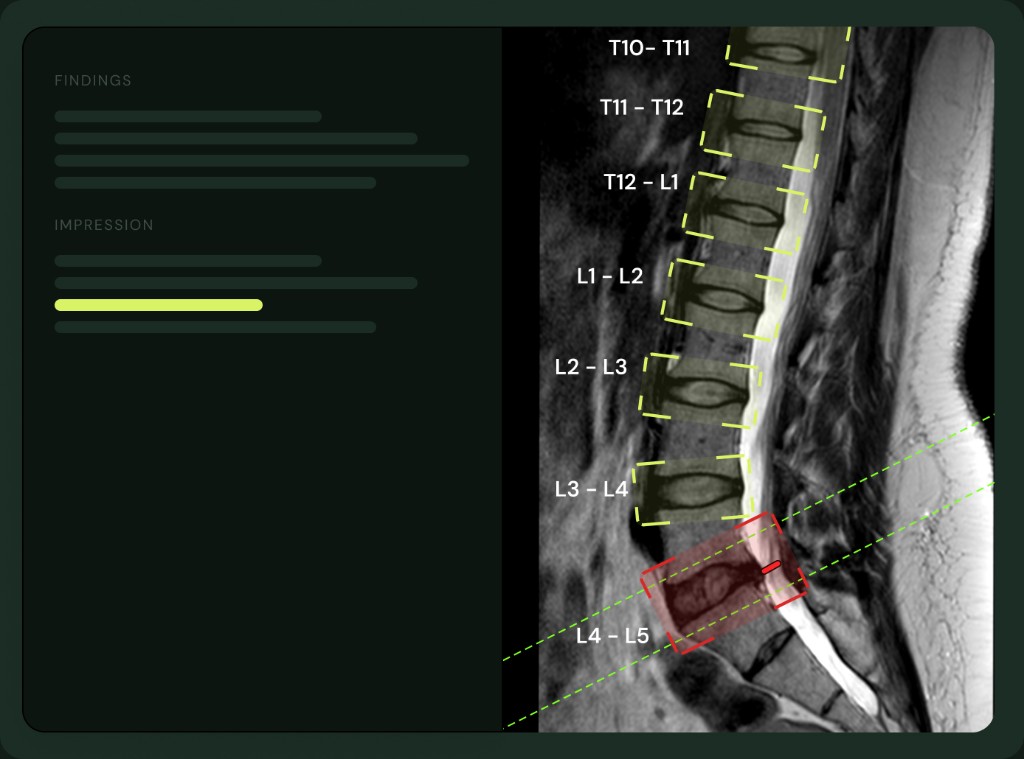

Old dot-phrase systems gave you a paragraph you still had to edit. Medsee gives you the scoring system itself, as a form. Pfirrmann 1 to 5 is a selector. Disc morphology is a toggle. Cord compression has its own red-flag section. You read the scan, grade what you see, and the report is written from your selections.

One-click Pfirrmann 1 to 5 grading per disc level, with disc morphology and stenosis grade alongside.

Pfirrmann, disc morphology, stenosis grade, canal narrowing, cord signal, and a red-flag section for cord compression.